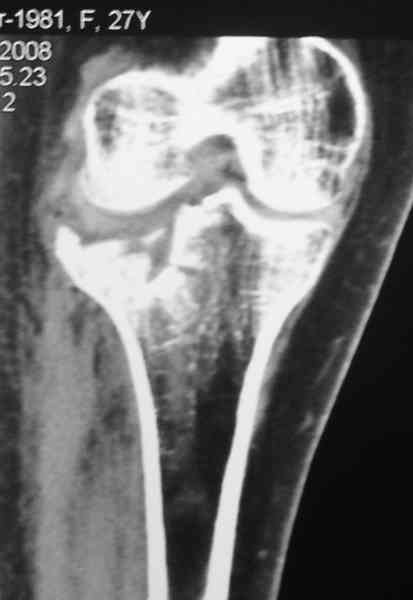

По тактике лечения, более импонирует второй вариант, но наружная плато расколота и туда при нагрузке внедряется н/мышелка бедра, поэтому после дистракции как репонирвать: или стяжными винтами, или изогнутами спицами или субхондральная костная пластика?

Уважаемый Абдурашид. Если нет противопоказаний , то из оперативных способов, я бы рекомендовал следующие: Полное замещение наружного мыщелка аллотрансплантатом либо открытая репозиция с элевацией и замещение дефекта ауто или аллокостью. В Ваших условиях , я бы рекомендовал второй способ. Во-время элевации необходимо разъединить фрагменты со стороны сустава ( надсечь скальпелем по линиям перелома, а затем тонким остеотомом их разъединить. При помощи долота произвести неполную остеотомию ( захватите не менее 1,5 - 2 см губчатой кости и поднять фрагменты, визуально отрепонировать и фиксировать 2-3 спицами. Дефект заместить костным ауто или аллатрансплантатом. Окончательная стабилизация пластиной ( лучше с угловой стабильностью, либо АВФ - позволит спокойно устранить угловую деформацию.

Недавно поступила больная через 1,5- 2 месяца.